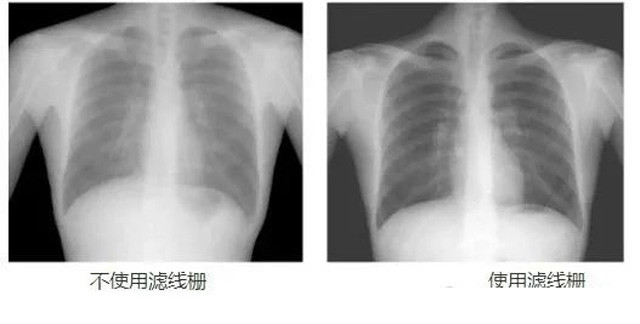

DR影像X射線在醫(yī)學(xué)檢查成像有著廣泛的使用。但是它的散射線影響成像質(zhì)量問題。濾線柵的發(fā)明使用很好的解決了這個(gè)問題,構(gòu)造簡(jiǎn)單鉛條粗,密度和柵比規(guī)格單一,能減散射線但吸收較多原發(fā)射線。伴隨這醫(yī)療影像設(shè)備技術(shù)的發(fā)展,這個(gè)濾線柵的工藝制造技術(shù)有改進(jìn),鉛條變薄,柵密度和柵比有更多的選擇。特別是材料方面有新組合,填充物也依不同成像要求優(yōu)化。特別是移動(dòng)DR這類型的DR設(shè)備的出現(xiàn),濾線柵也設(shè)計(jì)成立方便拆卸形的,方便使用。被照體情況決定是否使用,更好平衡成像質(zhì)量與射線劑量。

放置方面:置于人體與片盒間,聚焦面朝向X線入射方向,X線焦點(diǎn)放鉛條會(huì)聚線上,不能反置,X線中心對(duì)準(zhǔn)濾線柵中心,左右偏移不超3cm,傾斜X線管要與鉛條排列方向平行。攝影時(shí)焦距改變不超焦距的25%;活動(dòng)式濾線器運(yùn)動(dòng)時(shí)間至少長(zhǎng)于曝光時(shí)間的1/5;因吸收原發(fā)射線要適當(dāng)增加曝光條件;四肢薄位置一般不用濾線柵;不同千伏對(duì)應(yīng)不同柵比;立位胸片架、乳腺DR攝影等有各自特定濾線柵要求。